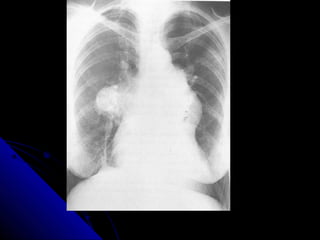

BBrroonncchhiieeccttaassiiss

RRiinngg sshhaaddoowwss,, aanndd hhoonneeyy ccoommbb..

TTrraammlliinnee sshhaaddoowwss..

TTuubbuullaarr sshhaaddoowwss..

GGlloovveedd ffiinnggeerr sshhaaddoowwss..